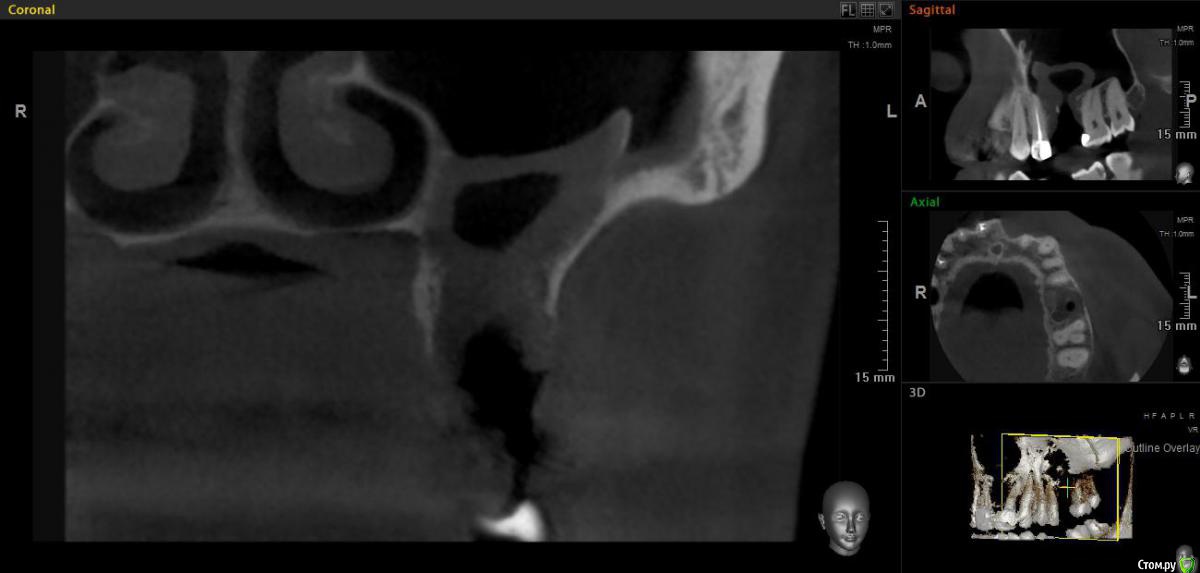

jm3300 Опубликовано 20 мая, 2019 Поделиться Опубликовано 20 мая, 2019 Добрый день. Пациент не мой, причины удаления, а так же о ходе удаления сказать ничего не могу. Известно лишь, что после удаления из лунки получили много зеленоватой жидкости. Удаляли с месяц назад. До сих пор имеется не сильно зияющая дырка. Нужно что то делать или просто ждать пока вторичным затянется. И если имплант планировать- ожидать ли там самостоятельного появления обьема кости? Ссылка на комментарий

L.E.S.I.K. Опубликовано 20 мая, 2019 Поделиться Опубликовано 20 мая, 2019 Я бы сделал ревизию через лунку, убрал оболочку кисты (похоже что она там осталась, или это эпителий врос - не важно) и провел бы закрытие небным лоскутом. При направлении в ЧЛХ есть вероятность, что наведут "разруху"(по Колддвел-Люк) и пациент получит проблему при дальнейшей реабилитации. З.Ы. На данных срезах не видно остиомеатальный комплекс- крайне желательно, чтобы он был не блокирован. 3 Ссылка на комментарий

Дмитрий М Опубликовано 21 мая, 2019 Поделиться Опубликовано 21 мая, 2019 месяц прошел, уже ничего не дождетесь, кость там не вырастет т.к. уже пошла эпителизация. так и останется не сильно зияющая дырка только вы видите клиническую картину, поэтому вам решать какой вариант лучше выбрать.в любом случае удалять кисту, оболочку, вероятно будет сообщение, которое необходимо закрывать и по ситуации готовиться к обоим вариантам по снимкам это скорее киста, (прослеживается кортикальная по контуру) 1 Ссылка на комментарий

Дмитрий Л. Опубликовано 21 мая, 2019 Поделиться Опубликовано 21 мая, 2019 Там уже есть сообщение с гайморовой. Возможно не функционирующее. Вяло текущий хронический воспалительный процесс. Ждать мало смысла. Если стремиться сделать всё как можно менее инвазивно, можно пойти по такому пути:1. Недельку попромывать соустье антисептиками. Воспаление стихнет. Десны добавится.2. Расскрыться. Аспирировать слизистую слюноотсосом. Кюретаж, всё через лунку. Если функционирующего соустья не было, оно появится.3. Небный лоскут, чтоб ушить соусье. Сосудосуживающие в нос, антибиотики. Ссылка на комментарий

jm3300 Опубликовано 21 мая, 2019 Автор Поделиться Опубликовано 21 мая, 2019 Ну по КТ и клинически сообщения с пазухой нет. Пациента,кроме наличия самой лунки, вообще ничего не беспокоит. Ссылка на комментарий